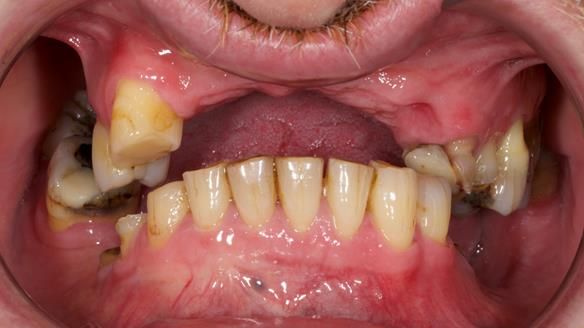

Keith’s combat denture case study

Keith’s case was one of the most challenging and rewarding cases I’ve treated this year. This 64 year old man presented with ill-fitting acrylic partial dentures that lacked stability, retention, and aesthetics. They constantly broke. He had lost the upper front teeth in a road traffic accident in his early 20s. The unopposed teeth had erupted, taking up space. After careful planning, we made a durable, metal-based upper partial denture/splint to address his dental concerns. He loved the outcome.